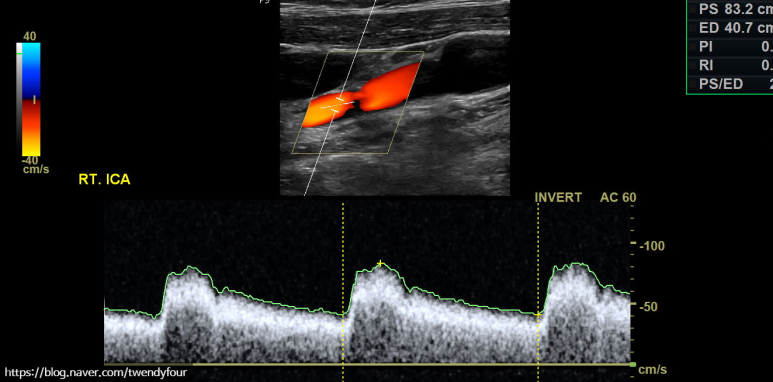

혈류 상태를 컬러로도 확인할 수 있으며, 경동맥 초음파를 정밀 도플러 검사로 혈류 속도를 측정합니다.이 검사를 통해 혈관 벽의 좁기 유무를 확인할 수 있어요.

경동맥의 혈액 순환 속도를 측정해 줍니다.

머리로의 좌측 내경동맥의 혈류속도를 확인하여 협착여부를 간접적으로 확인합니다.눈으로 얼마나 좁아졌는지도 중요하지만 사실 이 검사가 정말 중요합니다.